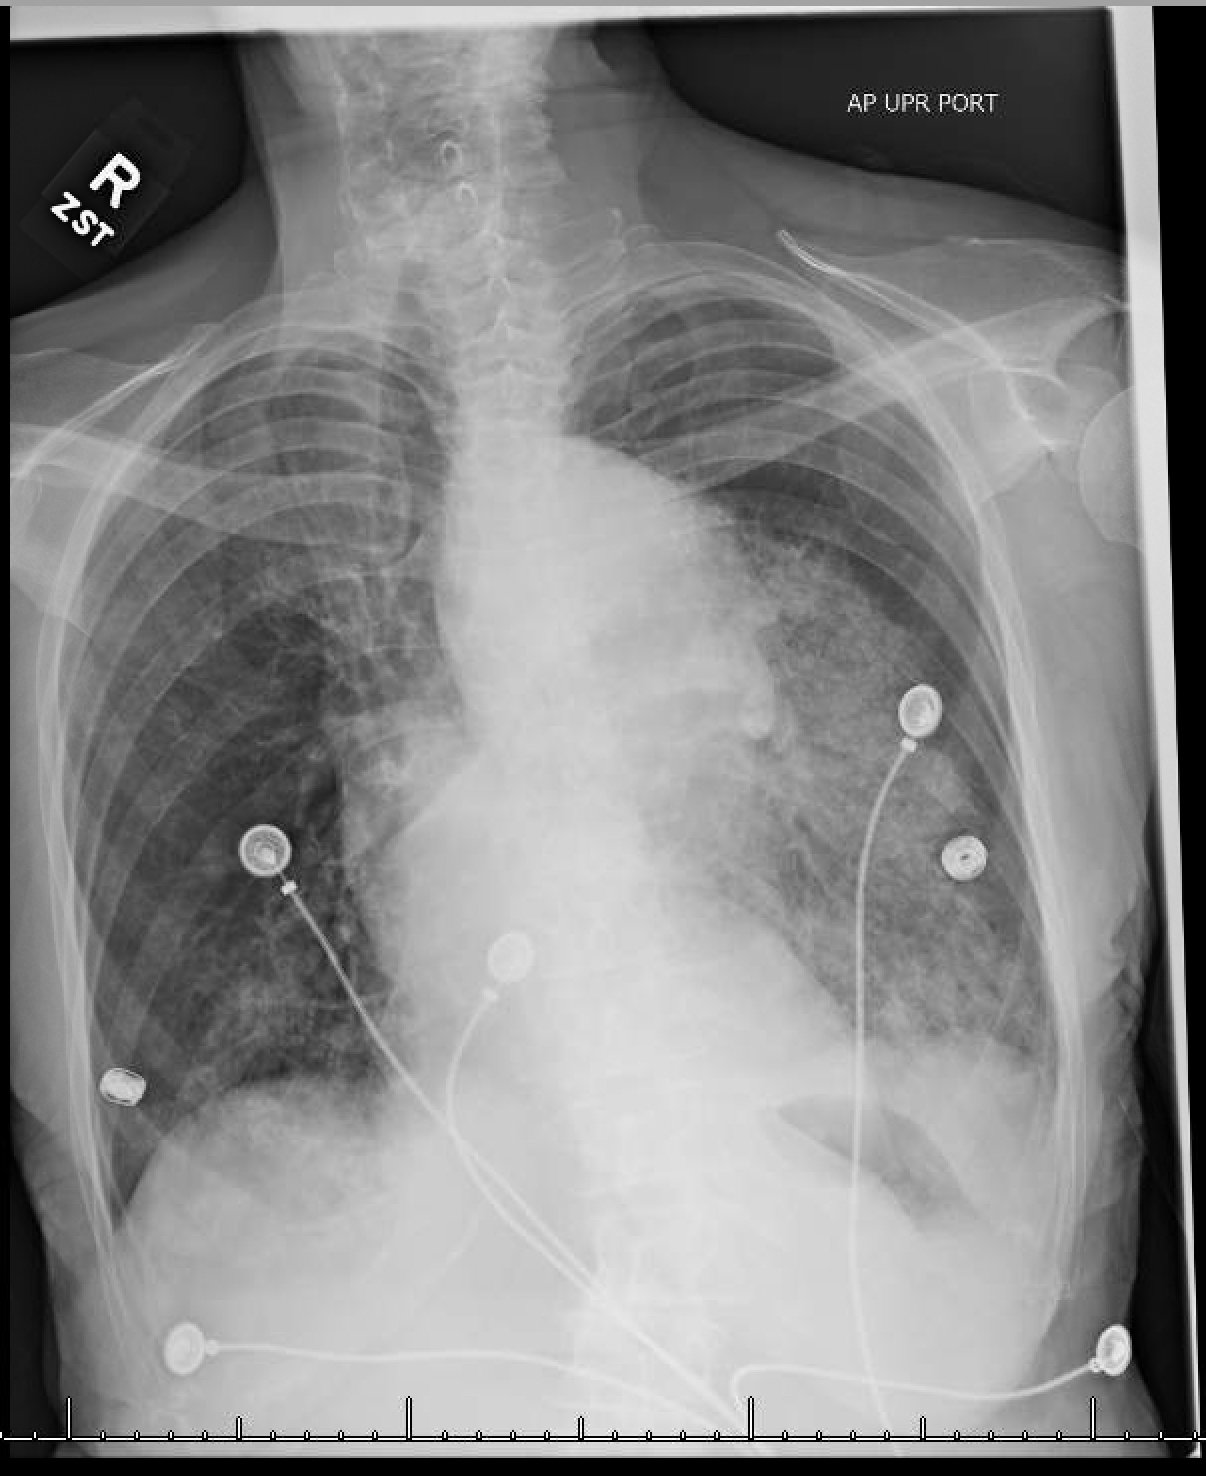

The patient’schest X-ray revealed a prominent mediastinum and opacification in the left middle and lower lung fields. The CT showed an aortic aneurysm extending from the thorax to the abdomen with rupture near T7 (blue arrow). It also showed periaortic hemorrhage with active extravasation (green arrow) likely secondary to a penetrating ulcer and bilateral pulmonary opacities concerning for hemothorax (pink arrow).

Thoracic aortic aneurysm (TAA) is a progressive and potentially deadly disease with a poor prognosis when left untreated.1 Most TAAs are asymptomatic and may be detected incidentally on imaging. Although presentation can vary, chest or back pain might be the first presenting symptom and can represent rapid expansion, acute dissection, or rupture.2 In the acute setting, chest X-ray might be the first imaging study performed during the initial evaluation of a patient with symptoms that suggest a potential for aortic disease. Predictive sensitivity of a widened mediastinum or abnormal aortic contour can be around 64% and 71% respectively, but the sensitivity of CXR is not adequate to definitively rule out acute aortic disease.3 CT with contrast remains the imaging study of choice for diagnosis of acute thoracic aortic disease; it can be nearly 100% sensitive and can also demonstrate the presence of a dissection flap or rupture.3